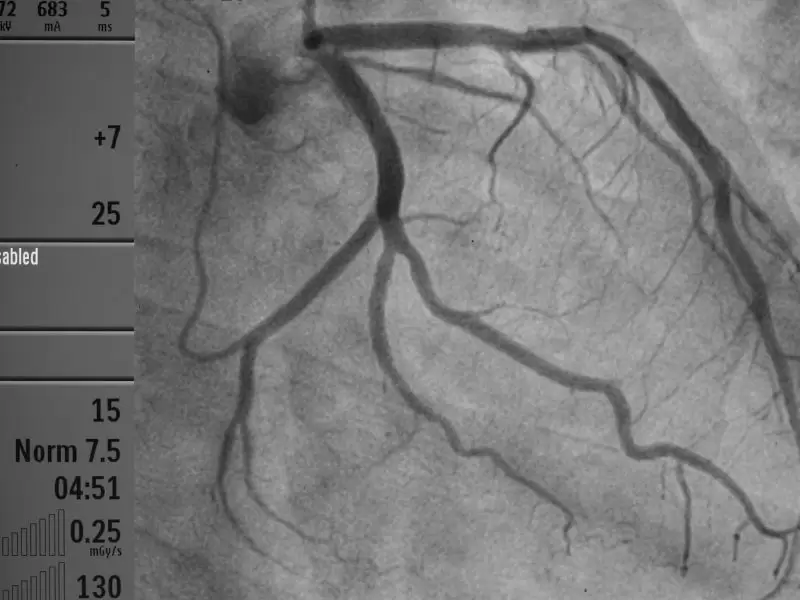

Sağlık Bakanlığı kalite yönetimine göre A Sınıfı (bölgenin en büyük kardiyoloji ve kalp damar cerrahisi) dal hastanesi olarak hizmet vermektedir. 40 standart oda, 2 engelli odası, 8 yatak üçüncü basamak Yoğun Bakım Ünitesi ,laminer floor sistemli 60’ar metrekare büyüklüğünde 3 ameliyathane salonu ve steril depo ,anjio salonu, röntgen, tomografi salonu bulunmaktadır.